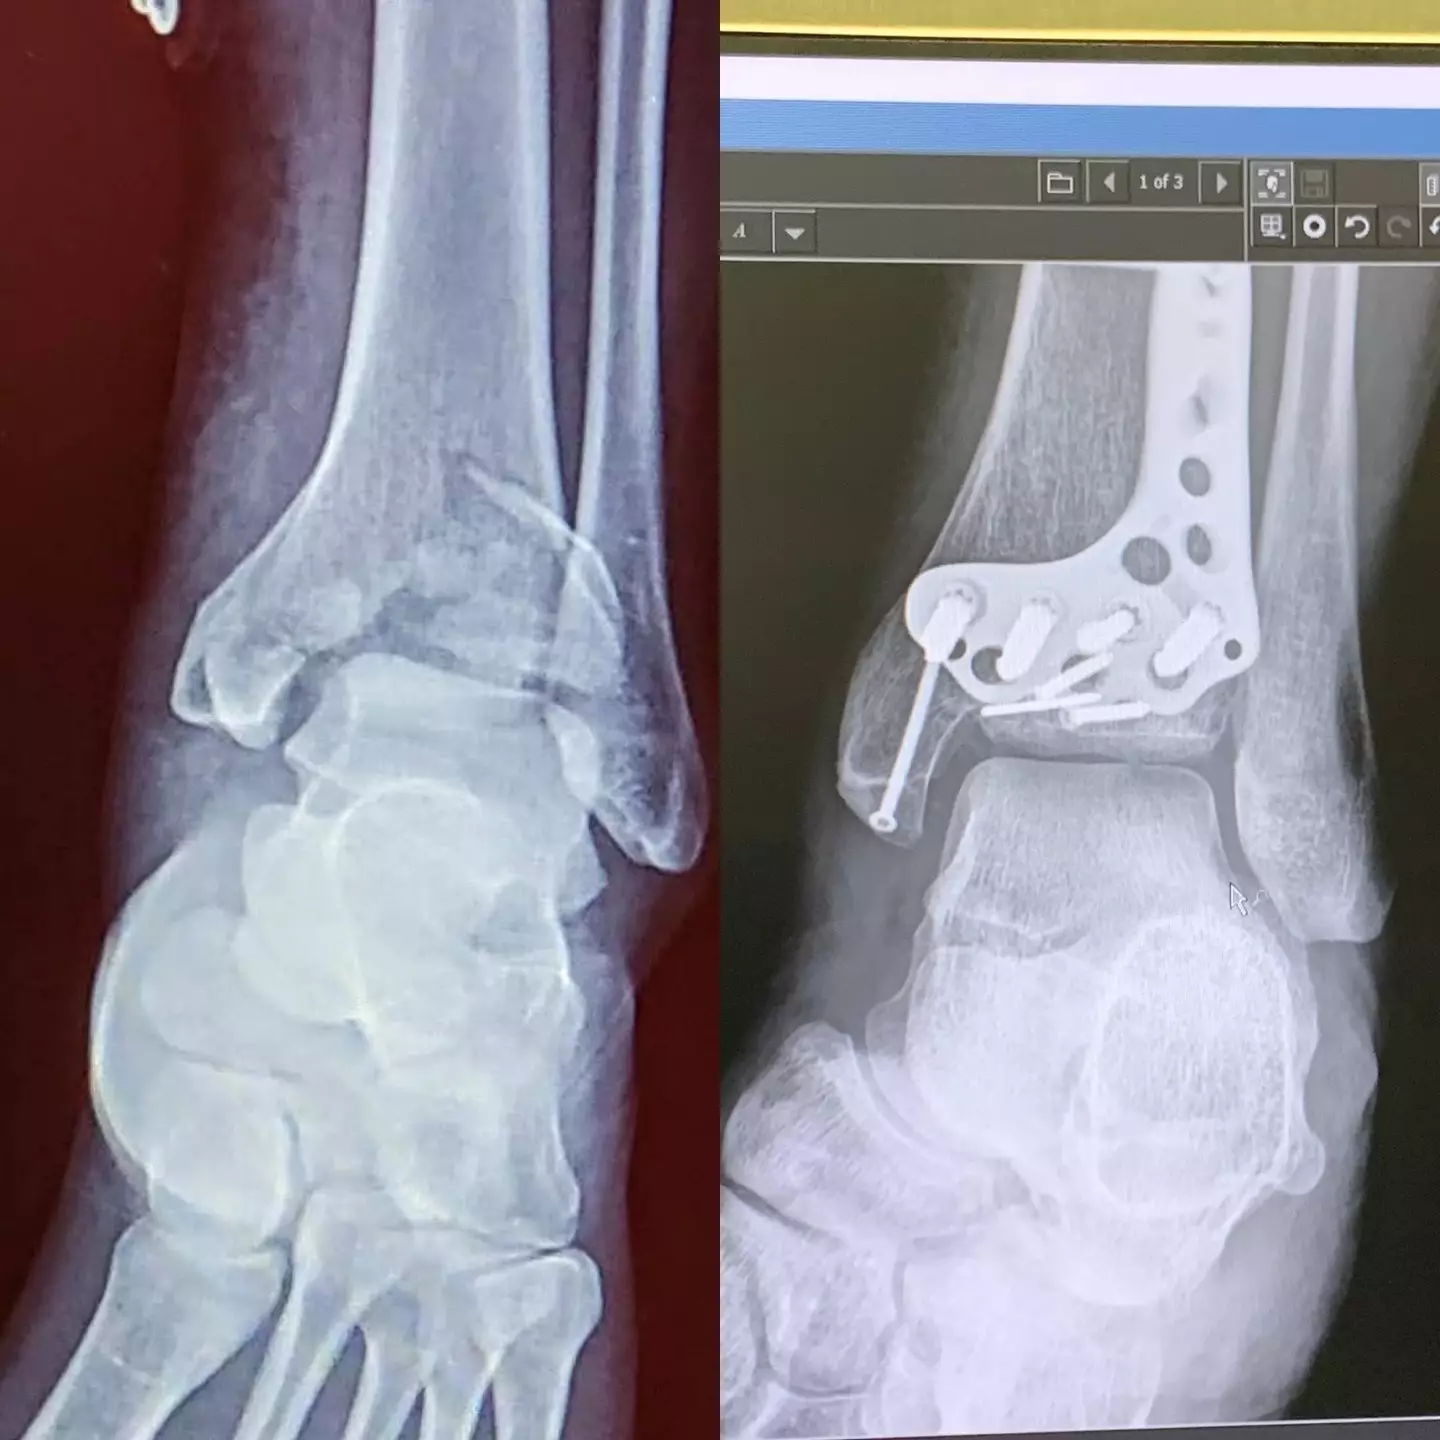

On top of that, Jordan tells us how she sustained a relatively rare, high-impact fracture called a pilon fracture.